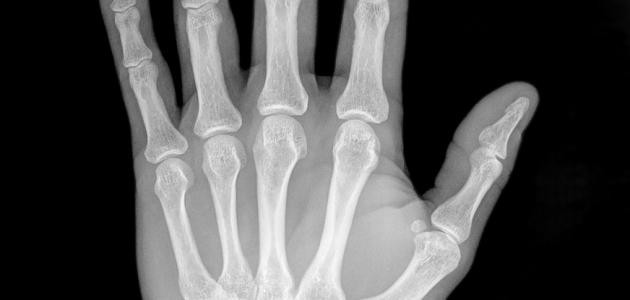

واستطاع رونتغن اكتشاف أشعّة إكس في عام 1895م، حين كان يجري تجربة تدفُّق التيّار الكهربائيّ في أنبوب زجاجيّ مُفرغ جزئيّاً من الهواء، وهو أنبوب أشعّة الكاثود؛ حيث لاحظ أنّ هناك ضوءاً قد نتجَ عن قطعة قريبة من البلاتين، وذلك عند تشغيل الأنبوب، فخرجَ بنظريّة، وهي أنّه عند اصطدام الإلكترونات (أشعّة الكاثود) بجدار الأنبوب الزجاجيّ، تظهرُ أشعّة مجهولة تُسبِّب وميضاً عند اصطدامها بالمادّة، ومن خلال عدّة ملاحظات، اكتشف أنّ هذا النوع من الأشعّة شفّاف لبعض الموادّ، مثل: الخشب، والورق، والألومنيوم، كما أنّ له تأثيراً في لوحات التصوير الفوتوغرافيّ، وهو لا يحمل أيّة خاصّية من خصائص الضوء، مثل: الانعكاس، أو الانكسار، ونتيجة لهذا، اعتقد بشكل خاطئ أنّه لا علاقة لهذا النوع من الأشعّة بالضوء، ونظراً لطبيعة هذه الأشعّة المجهولة، فقد أطلق عليها اسم أشعّة إكس، حيث التقطَ أوّل صورة باستخدام هذه الأشعّة لعظام يد زوجته.

بسبب مقدرة أشعّة إكس على اختراق موادّ مُعيَّنة، يتمّ استخدامها في عمليّات التفتيش الأمنيّ، وعند نَقْل البضائع والركّاب؛ حيث تسمحُ هذه الأشعّة، ومن خلال أجهزة الكَشْف عن الصور الإلكترونيّة، بتصوير محتويات الحقائب، والأمتعة، كما أنّها تُستخدَم في تصوير العِظام، وهي تُستخدَم كطريقة غير مُؤلِمة؛ لتشخيص المرض، ومراقبة العلاج، إضافة إلى أنّها تساعد في دَعْم العاملين في المجال الطبّي عند إدخالهم دعامات، أو أيّة أجهزة داخل الجسم، كما أنّ لها دوراً في علاج الأورام، وإزالة الانسدادات، والجلطات الدمويّة؛ وذلك لأنّ أشعّة إكس المُؤينة تُرسِّب كمّيات كبيرة من الطاقة في منطقة صغيرة؛ إذ تُجرِّد هذه الطاقة الإلكترونات من الذرّات، وهذا يؤدّي إلى تغيُّر في خصائصها الكيميائيّة، وكَسْرٍ للروابط الجزيئيّة، وبالتالي تَلَف الخلايا، أمّا إذا تمّ توجيهها إلى الخلايا السرطانيّة، فإنّها سوف تقتلها.

ويلجأ الطبيب إلى استخدام الأشعّة السينيّة؛ للمراقبة، ولتشخيص مرض مُعيَّن، أو مراقبة تطوُّر مرض تمّ تشخيصه، أو للتحقُّق من مدى فعاليّة ونجاح علاج ما، ولالتقاط صورة باستخدام أشعّة إكس، يتمّ ارتداء ملابس فضفاضة؛ لتحريكها بسهولة، بالإضافة إلى أنّه لا بُدّ من نَزْع أيّة مجوهرات، أو أيّ عناصر معدنيّة، وقد تستدعي الحاجة تناوُل مادّة مُتبايِنة، وظيفتها المساعدة في تحسين نوعيّة الصورة، حيث قد تحتوي هذه المادّة على مُركَّبات اليود، أو الباريوم.